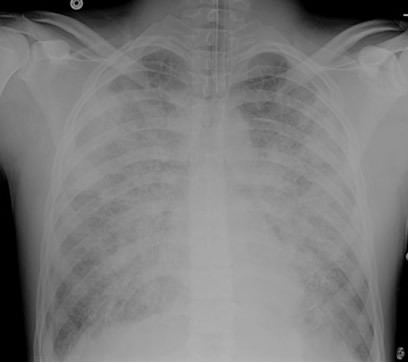

Initial CXR for the case found here:

(CXR source: http://radiopaedia.org/articles/normal-position-of-diaphragms-on-chest-radiography)